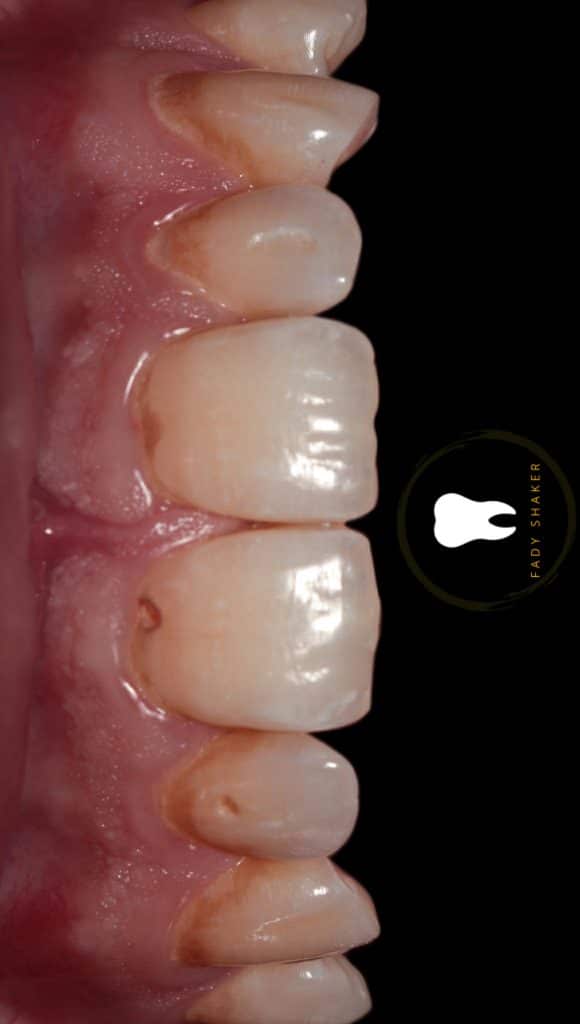

double class 5

not easy isolation game

16- immediate result & waiting for rehydration